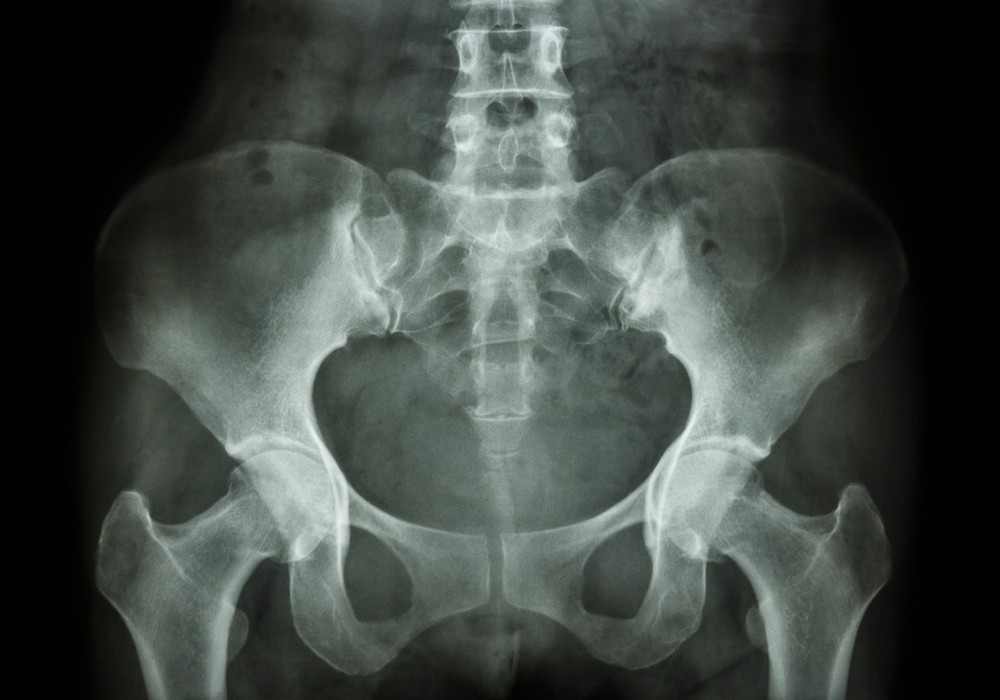

Что показывает рентген костей таза?

С помощью рентгенодиагностики обнаруживают переломы и трещины костей, ушибы, гематомы, остеомиелит, коксартроз, асептический некроз головки бедра, остеопороз, артрит. Такая методика позволяет диагностировать опухоли злокачественного и доброкачественного происхождения, остеохондропатии, аномалии развития, дисплазии, метастазы, инфекционные процессы, воспаления.